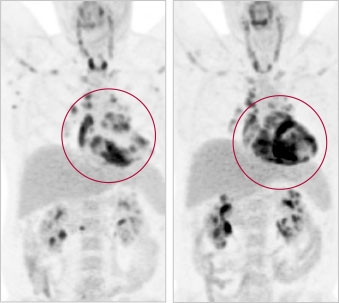

• Nuclear imaging, such as positron emission tomography (PET): to measure inflammation and activity in different areas of the heart, using tiny amounts of radioactive compounds